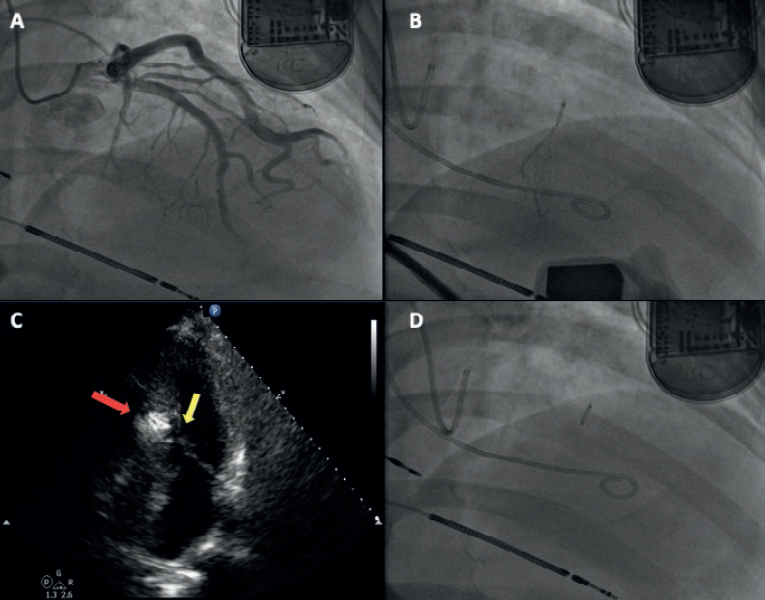

A bail-out alcohol septal ablation procedure was attempted that showed a 65-mmHg intraventricular gradient. After the 110-mmHg extrasystole bubble contrast was injected to choose the target septal branch (figure 3) followed by the injection of 0.1 mL of alcohol per millimeter of contrasted septum. In the echocardiography a 23 mm contrasted septum was measured, and 2.3 mL of alcohol were administered in the second septal branch.

Figure 3. A: coronary angiography. B: injection of bubble contrast in the second septal branch. C: contrast enhancement of the susceptible septal region (arrow). D: over-the-wire balloon used for the administration of alcohol.